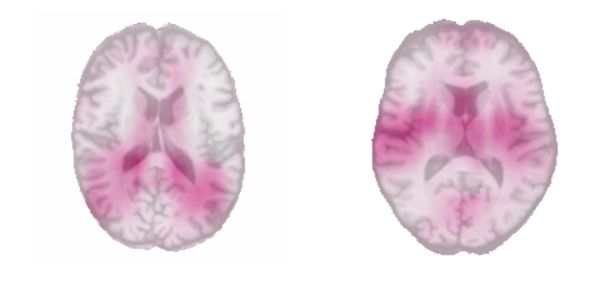

在首次了解黑盒时,我们使用了一种简单的遮挡技术。该想法是遮住测试集图像的小区域(此处为 4 平方厘米),并观察对应的平均绝对误差下降。如果性能显著下降,则说明遮住的区域对算法非常重要。在下图中,粉色区域与最大误差下降有关:

30 岁以下(左图)和 60 岁以上(右图)成年受试者的遮挡图

左图最年轻受试者的遮挡图表明:最靠近脑室的区域是预测中的重要区域。从科学角度来看,此结论成立。我们知道,年轻人的脑室是最薄的,因为它会随年龄的增长而扩张。对于年龄最大的受试者而言,其遮挡图揭示了两侧岛叶的重要性,这与 Good 等,2001 的研究结果一致。